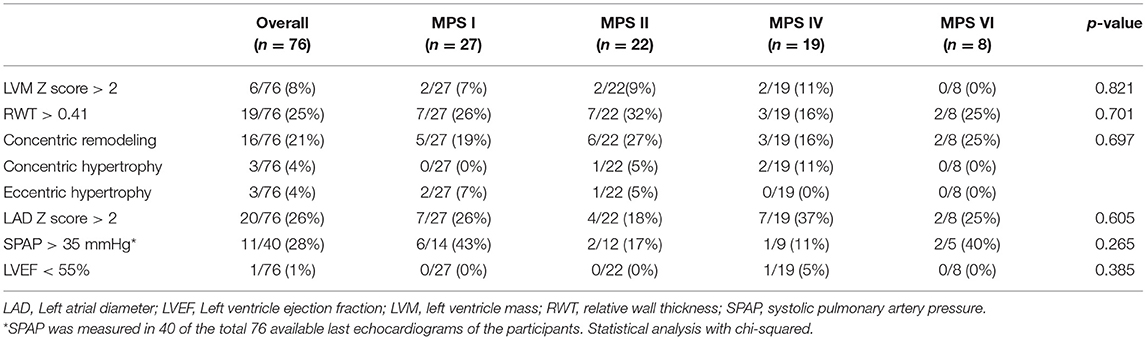

Left ventricular hypertrophy parameters, including LVPWT, IVST Z scores, and RWT, were above average in a significant proportion of patients in all subgroups (Figure 3). Nevertheless, LVM Z scores were normal in the last available echocardiogram of most of the patients (Table 2). Signs of left ventricular hypertrophy were more commonly observed in children than in adults (Table 3).

Table 4. Prevalence of echocardiographic abnormalities at the last available echocardiogram, including both ERT treated and untreated subjects.